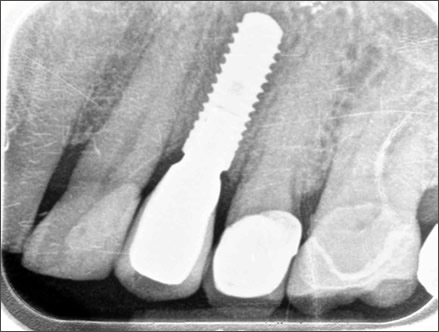

Dental implants are the best-known treatment to replace single or multiple missing teeth because they feel and behave just like natural teeth. After a while you won’t be able to tell the difference – even forgetting that they are there.

The procedure to place implants and replace a missing tooth or multiple teeth is straightforward as there is little need to treat surrounding teeth. Once a crown is placed over the implant it will appear indistinguishable from the natural teeth.